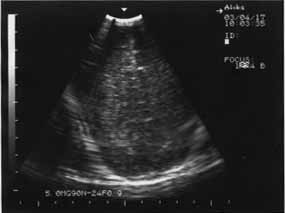

Кроме того, ишемический некроз проявляется повышением эхогенности обычно в острой фазе. В подострой и хронической фазах ведущую роль в диагностике играют неоднородность структуры, а также наличие участков с различной эхогенностью, в том числе кист. ПВЛ в подавляющем числе наблюдений является двусторонним процессом (рис. 1,2).

Рис. 1 Новорожденная Б 11 суток, СГ – 29 недель, ПВЛ III-IV степени на фоне повышенной эхогенности – мелкие анэхогенные образования (формирование кист). | Рис. 2. 10 суток, СГ – 30 недель, ПВЛ III степени, гиперэхогенность в перивентрикулярном пространстве (до образования кист). |

Эхографическое выявление острой фазы ПВЛ в первые сутки жизни может быть затруднительным. Это обстоятельство диктует необходимость динамического эхографического наблюдения за недоношенными детьми независимо от наличия или отсутствия у них морфологической картины поражения ЦНС в первые трое или даже семь суток жизни. С момента начала некротического процесса в веществе мозга до образования кисты обычно проходит 10-14 дней (рис.1,2). Во всех случаях перивентрикулярный некроз со временем приводит к пассивной внутренней гидроцефалии, которая может развиться через 2-3 недели после рождения.